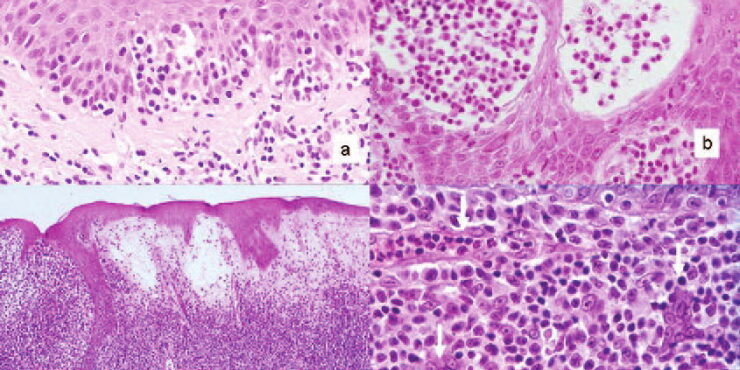

Read MoreMunro microabscesses in Psoriasis = خراجات مونرو المجهرية في الصدف Psoriasis Psoriasis may be divided into psoriasis vulgaris, generalized pustular psoriasis, and localized pustular psoriasis. Psoriasis Vulgaris Clinical Features Psoriasis vulgaris is a common chronic inflammatory skin disorder that affects approximately 1.5% to 2% of the population in the Western countries. It is characterized by […]